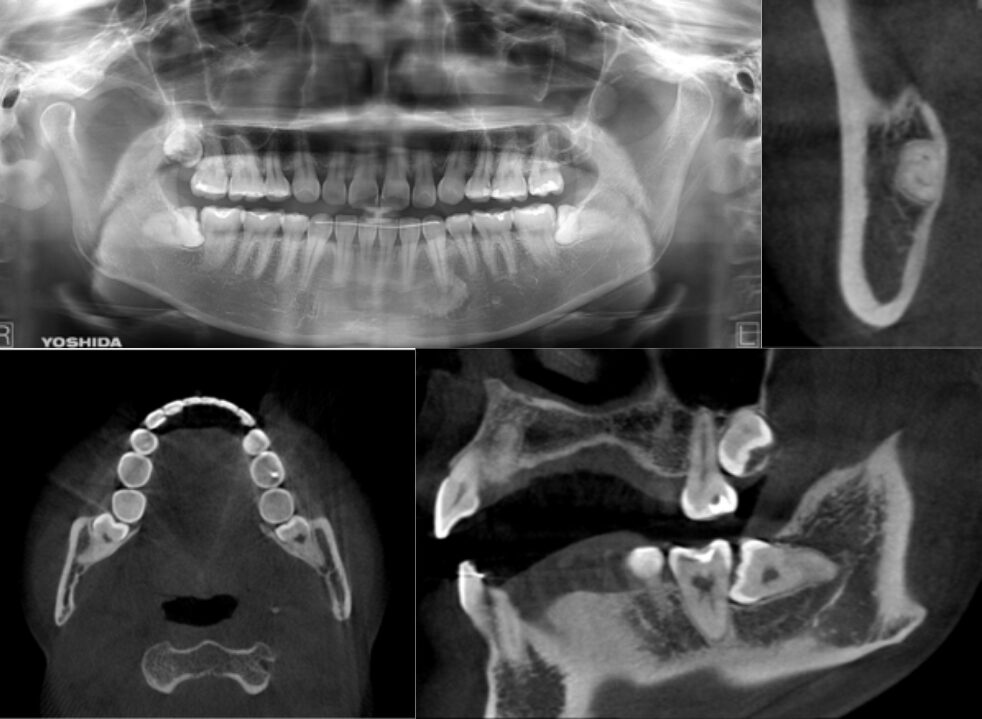

冠状断にて2根 矢状断にて最大豊隆部付近まで下顎枝が被覆している症例

| 患者情報 | 23歳 女性 |

| 手術時間 | 10分 |

| 治療内容 | 親知らず抜歯 |

| グレゴリー分類 | クラスⅡ position B |